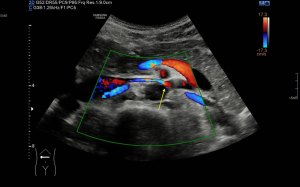

Los vientres anteriores de los Músculos Digástricos derecho e izquierdo forman los bordes laterales del triángulo submentoniano, mira:

En este triángulo lo que vas a encontrar son ganglios.

Los vientres anteriores de los músculos Digástricos, que son el objeto del desarrollo de este Post, son dos estructuras musculares redondeadas en el corte transversal, imagen 1, y alargados si los estudiamos en el eje largo, imagen 3, mira:

Ecográficamente los músculos digástricos en eje corto tienen semiología hipoecogénica, en aspecto de noche estrellada, como la de hoy, y en el eje largo en forma de penacho o en forma de plumas con las fibras alargadas y paralelas a la superficie.